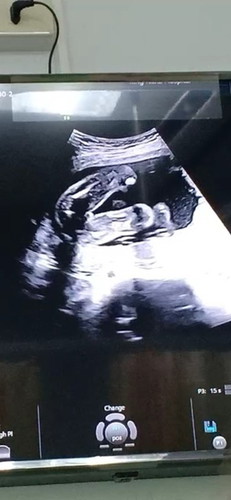

อัลตราซาวนด์

ใครดูออกบ้างคะ ว่าน้องเป็น ชายหรือหญิง คุณหมอไม่ได้ระบุเพศให้

ที่โผล่ๆ นี่จู๋น้อง หรือมุมอื่นมาพาดทาบภาพก็ไม่รู้นะคะ 😆😆 พบหมอรอบหน้า เอาภาพไปถามหมออีกรอบค่ะ

แล้วหมอไม่ได้บอกหรอค่ะตอนซาวด์ว่าหญิงหรือชาย ถ้าเท่าที่เขาดูคือหญิงนะค่ะ เพราะไม่มี อะไรชร้ออกมา